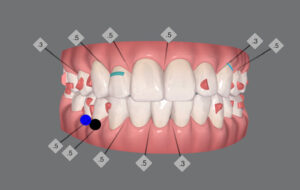

🔶アフター🔶

正面

右

予想通り

右上の歯がグラグラしてきたので

次回は ここにインプラント

続く